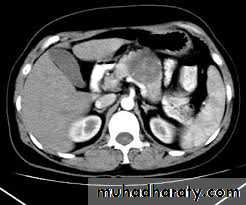

 Ultrasound Scan  Histology & cytology

 CT Scan  Angiography

 MR Imaging  Laparoscopy

 ERCP

3. Pre-operative localization of the tumour very important identification at operation can be difficult.[Combination CT Scan and selective angiography]